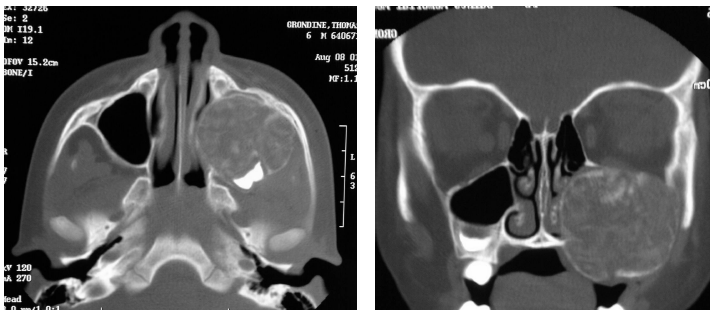

osteosarcoma

a malignant tumor of bone-forming tissue

most common primary malignant tumor of bone in patients under 40 years of age

gnathic

extragnathic

treatment: surgery, adjuvant chemotherapy, radiotherapy

gnathic osteosarcoma

3rd and 4th decades

extragnathic osteosarcoma

long bones

10-20 year olds

osteosarcoma radiographic features

“sun ray” or “sun burst” appearance

widening of the PDL of involved teeth